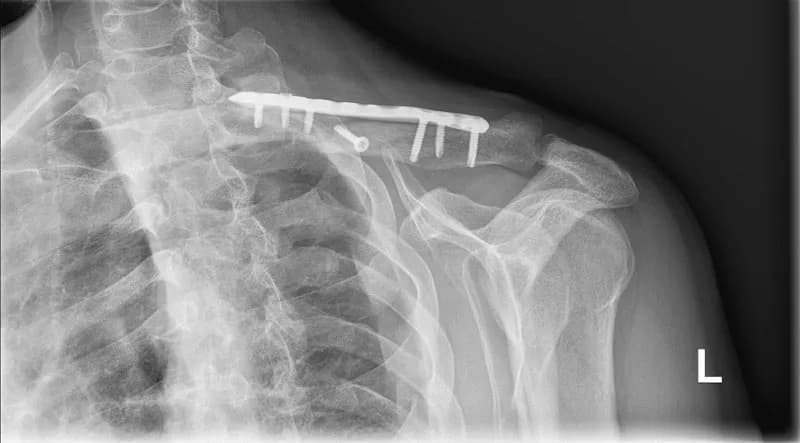

Rehabilitacja po złamaniu obojczyka to proces, który trwa zazwyczaj od 3 do 6 miesięcy. Czas ten może się różnić w zależności od wielu czynników, takich jak rodzaj złamania czy wiek pacjenta. W przypadku prostych złamań bez przemieszczenia, rehabilitacja przebiega szybciej, jednak bardziej skomplikowane złamania mogą wydłużyć czas leczenia. Warto zrozumieć, co wpływa na ten proces, aby lepiej przygotować się na powrót do pełnej sprawności.

Rehabilitacja po złamaniu obojczyka składa się z kilku kluczowych etapów, które są niezbędne do pełnego powrotu do zdrowia. Pierwszym z nich jest etap immobilizacji, który zazwyczaj trwa od 2 do 4 tygodni. W tym czasie pacjent nosi specjalny opatrunek lub temblak, co pozwala na stabilizację złamanej kości. To ważny moment, ponieważ odpowiednia immobilizacja jest kluczowa dla prawidłowego gojenia się obojczyka.